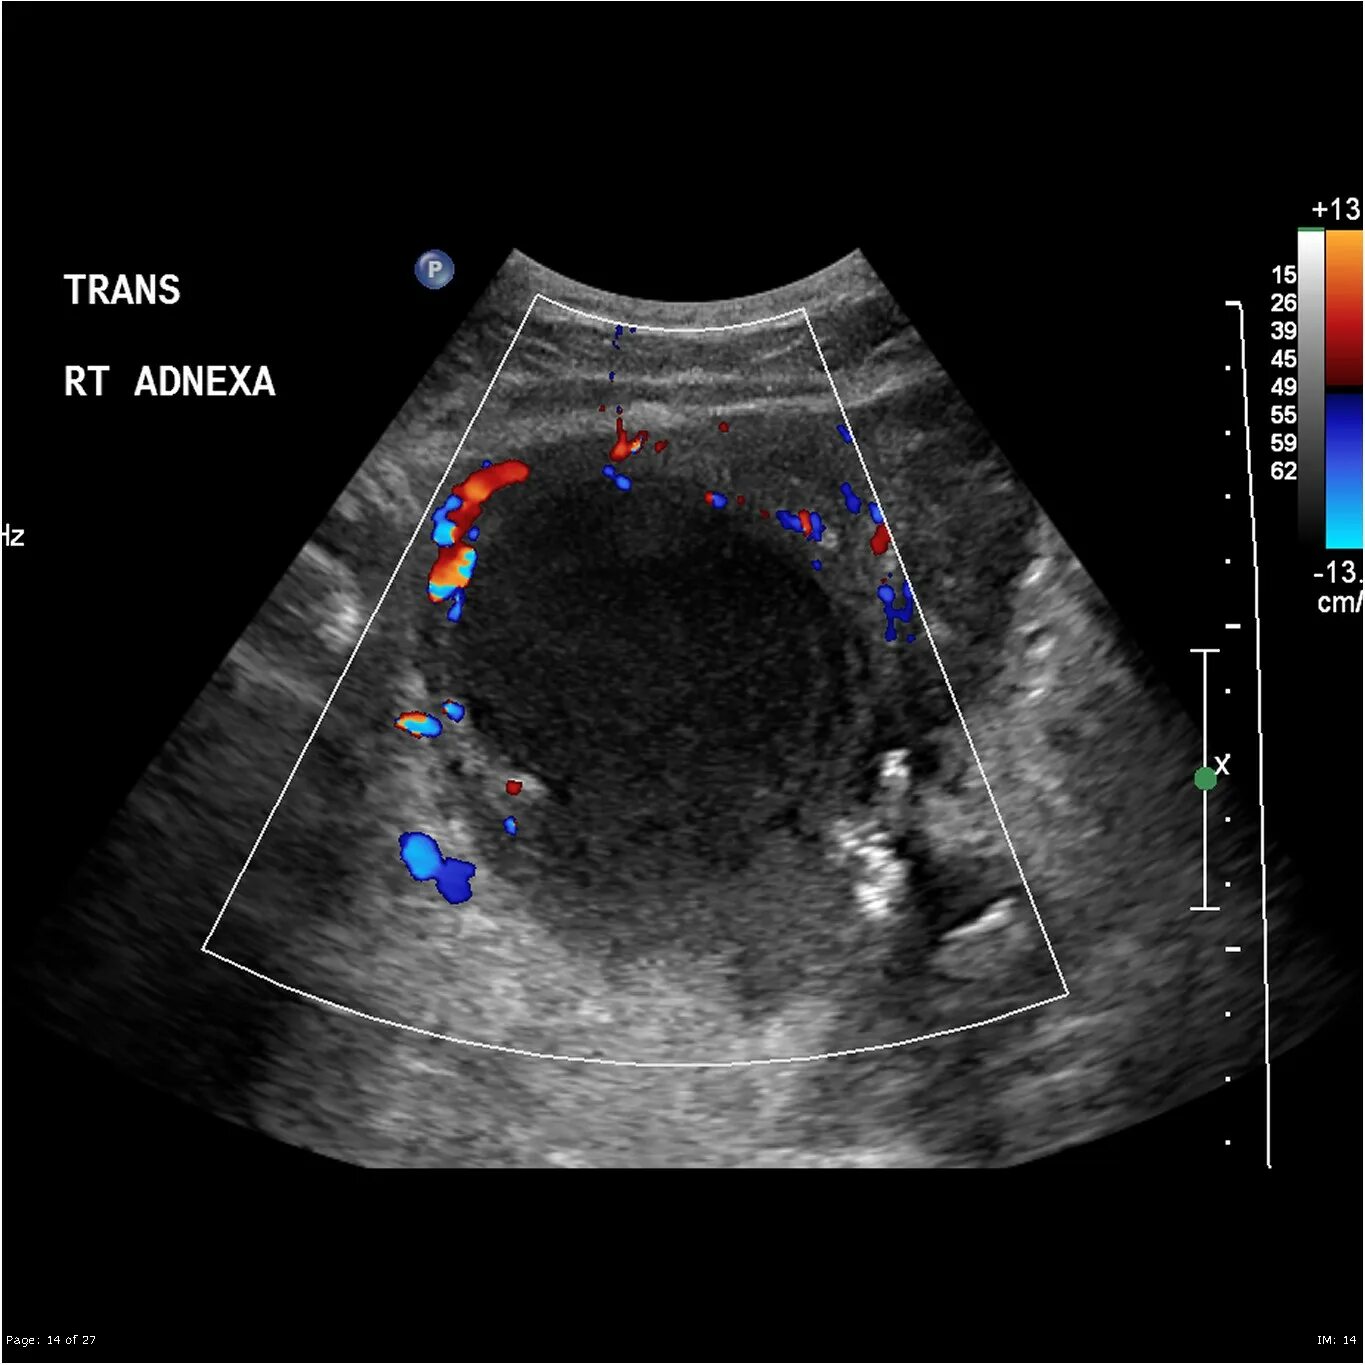

Ультразвуковое исследование забрюшинного пространства